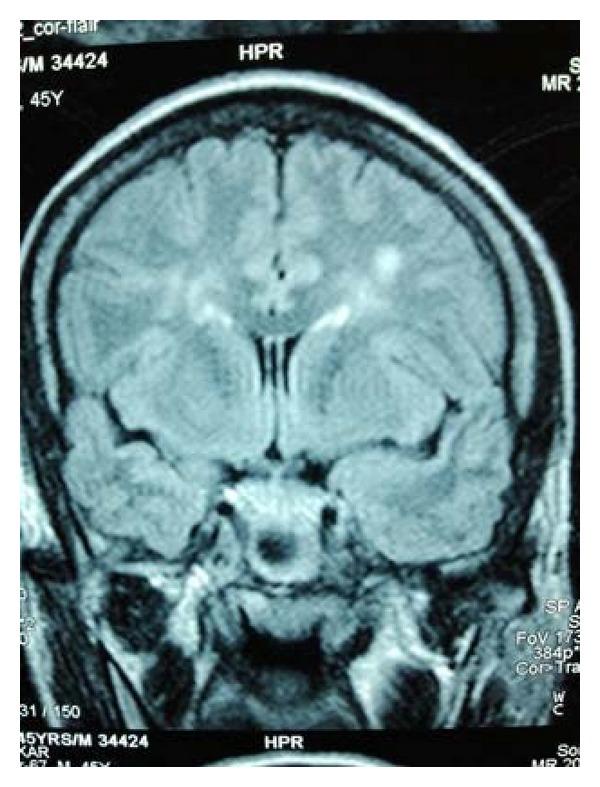

Cirrhotic or hepatic myelopathy is a rare neurological complication of chronic liver disease usually seen in adults and presents as a progressive pure motor spastic paraparesis which is usually associated with overt liver failure and a surgical or spontaneous systemic portocaval shunt. We describe the development of progressive spastic paraparesis, in a patient with alcoholic cirrhosis with portal hypertension and portal colopathy who presented with the first episode of hepatic encephalopathy. The patient had not undergone any shunt procedure.